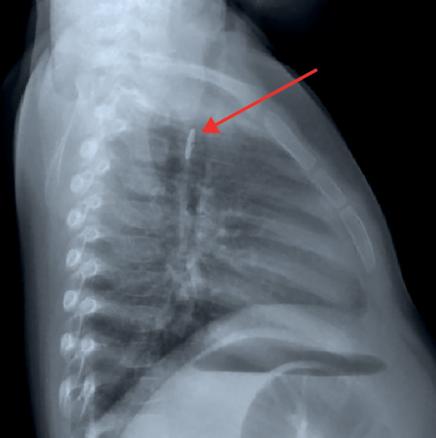

Chez l’enfant, les jouets ou leurs composants (notamment des piles boutons, fig. 2) et les pièces de monnaie sont en cause dans 50 à 70 % des cas, mais provoquent rarement des blessures profondes ou perforantes. Dans la population adulte, les « intrus » sont souvent alimentaires (os, arêtes, viande… chez deux tiers des sujets) ; parfois, il s’agit d’objets plus volumineux (prothèse dentaire, comme chez cette patiente) ou plus acérés (cure-dent, épingles…).